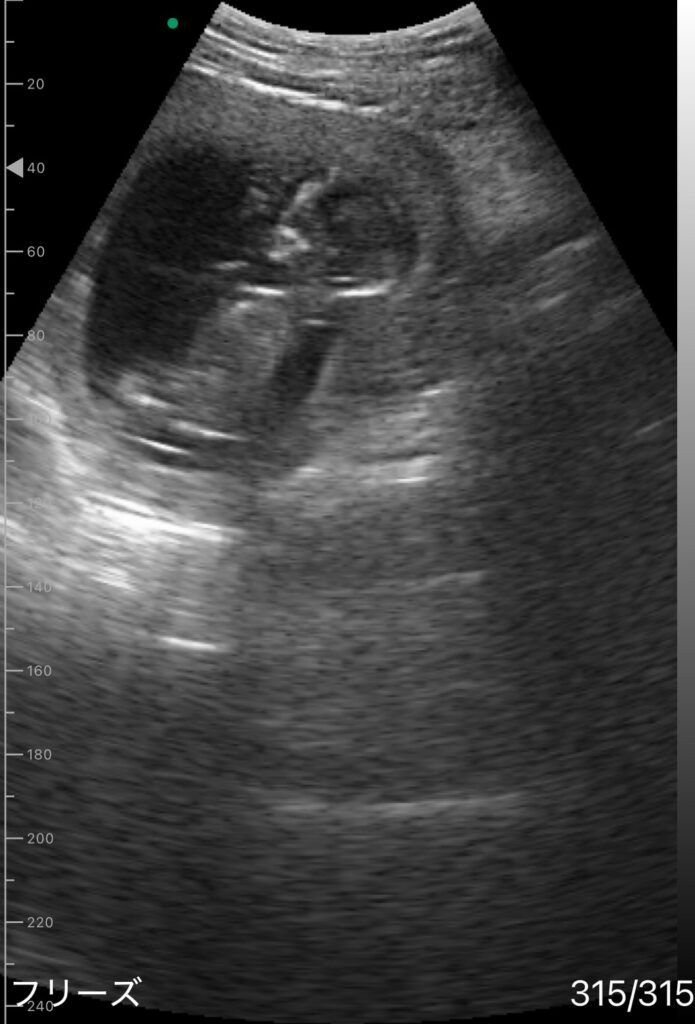

エコー写真②(@iiyl_llyiさんより提供)